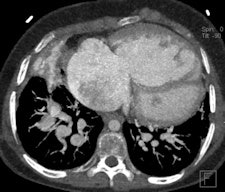

MDCT using a low radiation dose protocol is the best diagnostic tool for assessing the central airway, cardiovascular and mediastinal abnormalities, and the lung parenchyma in children, and the relevant information can be acquired with a single-volumetric data set acquisition, she stated. Using thin-slice collimation acquisition with inherent isotropic resolution, the image data can be manipulated and reformatted to display 2D and 3D images with the same spatial resolution as the axial images, thus enhancing diagnostic accuracy and providing data that can be used in presurgical planning and patient management.